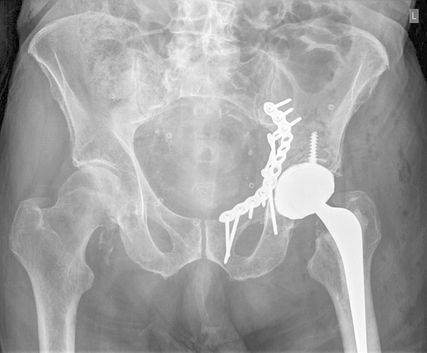

Die Mehrheit der Herausforderungen bei der Behandlung der Fragilitätsfraktur des Acetabulums überschneidet sich mit denen bei Beckenringfraktur. Ebenso wenig überraschend treten auch auf der anderen Seite des Hüftgelenkes ähnliche Komplikationen und eine Reduktion der Lebenserwartung wie bei hüftnahen Oberschenkelfrakturen auf. Im Unterschied zu den FFP gilt dieselbe Klassifikation für Hochrasanz- und Niedrigenergietraumata des Acetabulums nach Judet und Letournel. Der große Unterschied besteht jedoch in der Häufigkeitsverteilung. Aufgrund der meist einfachen Stürze mit Gewalteinwirkung über den Trochanter major betreffen die Fragilitätsfrakturen des Acetabulums meist den vorderen Pfeiler und die quadrilaterale Fläche. Entsprechend sind dislozierte Frakturen eine Domäne der offenen Operationsverfahren und der Hüftendoprothetik. Der Stellenwert der minimalinvasiven Stabilisierung nicht dislozierter Acetabulumfrakturen und der Stabilisierungen in Fehlstellung ist wissenschaftlich nicht geklärt. Jedoch gibt es zunehmende Literatur über das sogenannte „fix and replace“, bei dem eine Osteosynthese eines Pfeilers mit einer primären Totalendoprothese in einer Operation kombiniert wird (Abb. 2).

Abb. 2: „Fix and replace“ mit Osteosynthese und Hüfttotalendoprothese in der selben Operation bei geriatrischer Acetabulumfraktur mit Impressionsfraktur des Doms

Bisher konnten dabei keine erhöhten Komplikationsraten gegenüber der konventionellen Osteosynthese festgestellt werden. Gleichzeitig besteht aber der Vorteil der Vollbelastbarkeit, des Einsatzes einer konventionellen Pfanne und der in der Orthogeriatrie erwünschten „one-shot surgery“ (nur eine Operation statt einer potenziellen zweiten Operation bei Versagen der Osteosynthese und sekundärer Prothese). Bei ca. 30% der geriatrischen Acetabulum-Osteosynthesen in der Literatur erfolgte eine Revision mittels Prothese. Risikofaktoren für die Notwendigkeit einer sekundären Hüfttotalendoprothese nach Osteosynthese sind: höheres Alter, Impressionsfrakturen des Doms und Hüftkopfes, Medialisierung des Hüftkopfes („zentrale Hüftluxation“), nichtanatomische Reposition (häufig durch späte Versorgung nach konservativem Therapieversuch oder längerer Operationsvorbereitung bei Multimorbidität).

Die „Fix and replace“-Behandlungsoption ist gerade für Zwei-Pfeiler-Frakturen interessant, da bei dieser häufigen geriatrischen Frakturform aufgrund der vorliegenden sakroiliakalgelenksnahen Beckendiskontinuität selbst durch gängige Revisionspfannen nicht immer eine Belastungsstabilität erreicht werden kann (Abb. 3).

Im Gegenzug dazu wird in der Literatur auch eine minimalinvasive offene Osteosynthese beschrieben, wobei man auf ausgedehnte Repositionsmanöver mit dem damit verbundenen Blutverlust verzichtet. Dadurch werden zum Teil verbliebene Fehlstellungen akzeptiert bzw. wird durch postoperative Mobilisierung eine sekundäre Dislokation in Kauf genommen, um eine postoperative Vollbelastung zu ermöglichen. Eine entsprechende Operationstechnik über einen Stoppa-Zugang und mit Plattendesign mit Abstützung der quadrilateralen Fläche wurde durch Culemann 2023 anschaulich beschrieben.12 Bei geschwächter Knochenqualität ist neben dem Plattendesign mit medialer Abstützung an der quadrilateralen Fläche auch das Augenmerk auf eine stabile Verankerung zu legen. Die infraacetabuläre hintere Pfeiler-Schraube, welche meist um die 100mm Länge aufweist, ist hierbei sehr empfehlenswert (Abb. 2 und Culemann 202312).